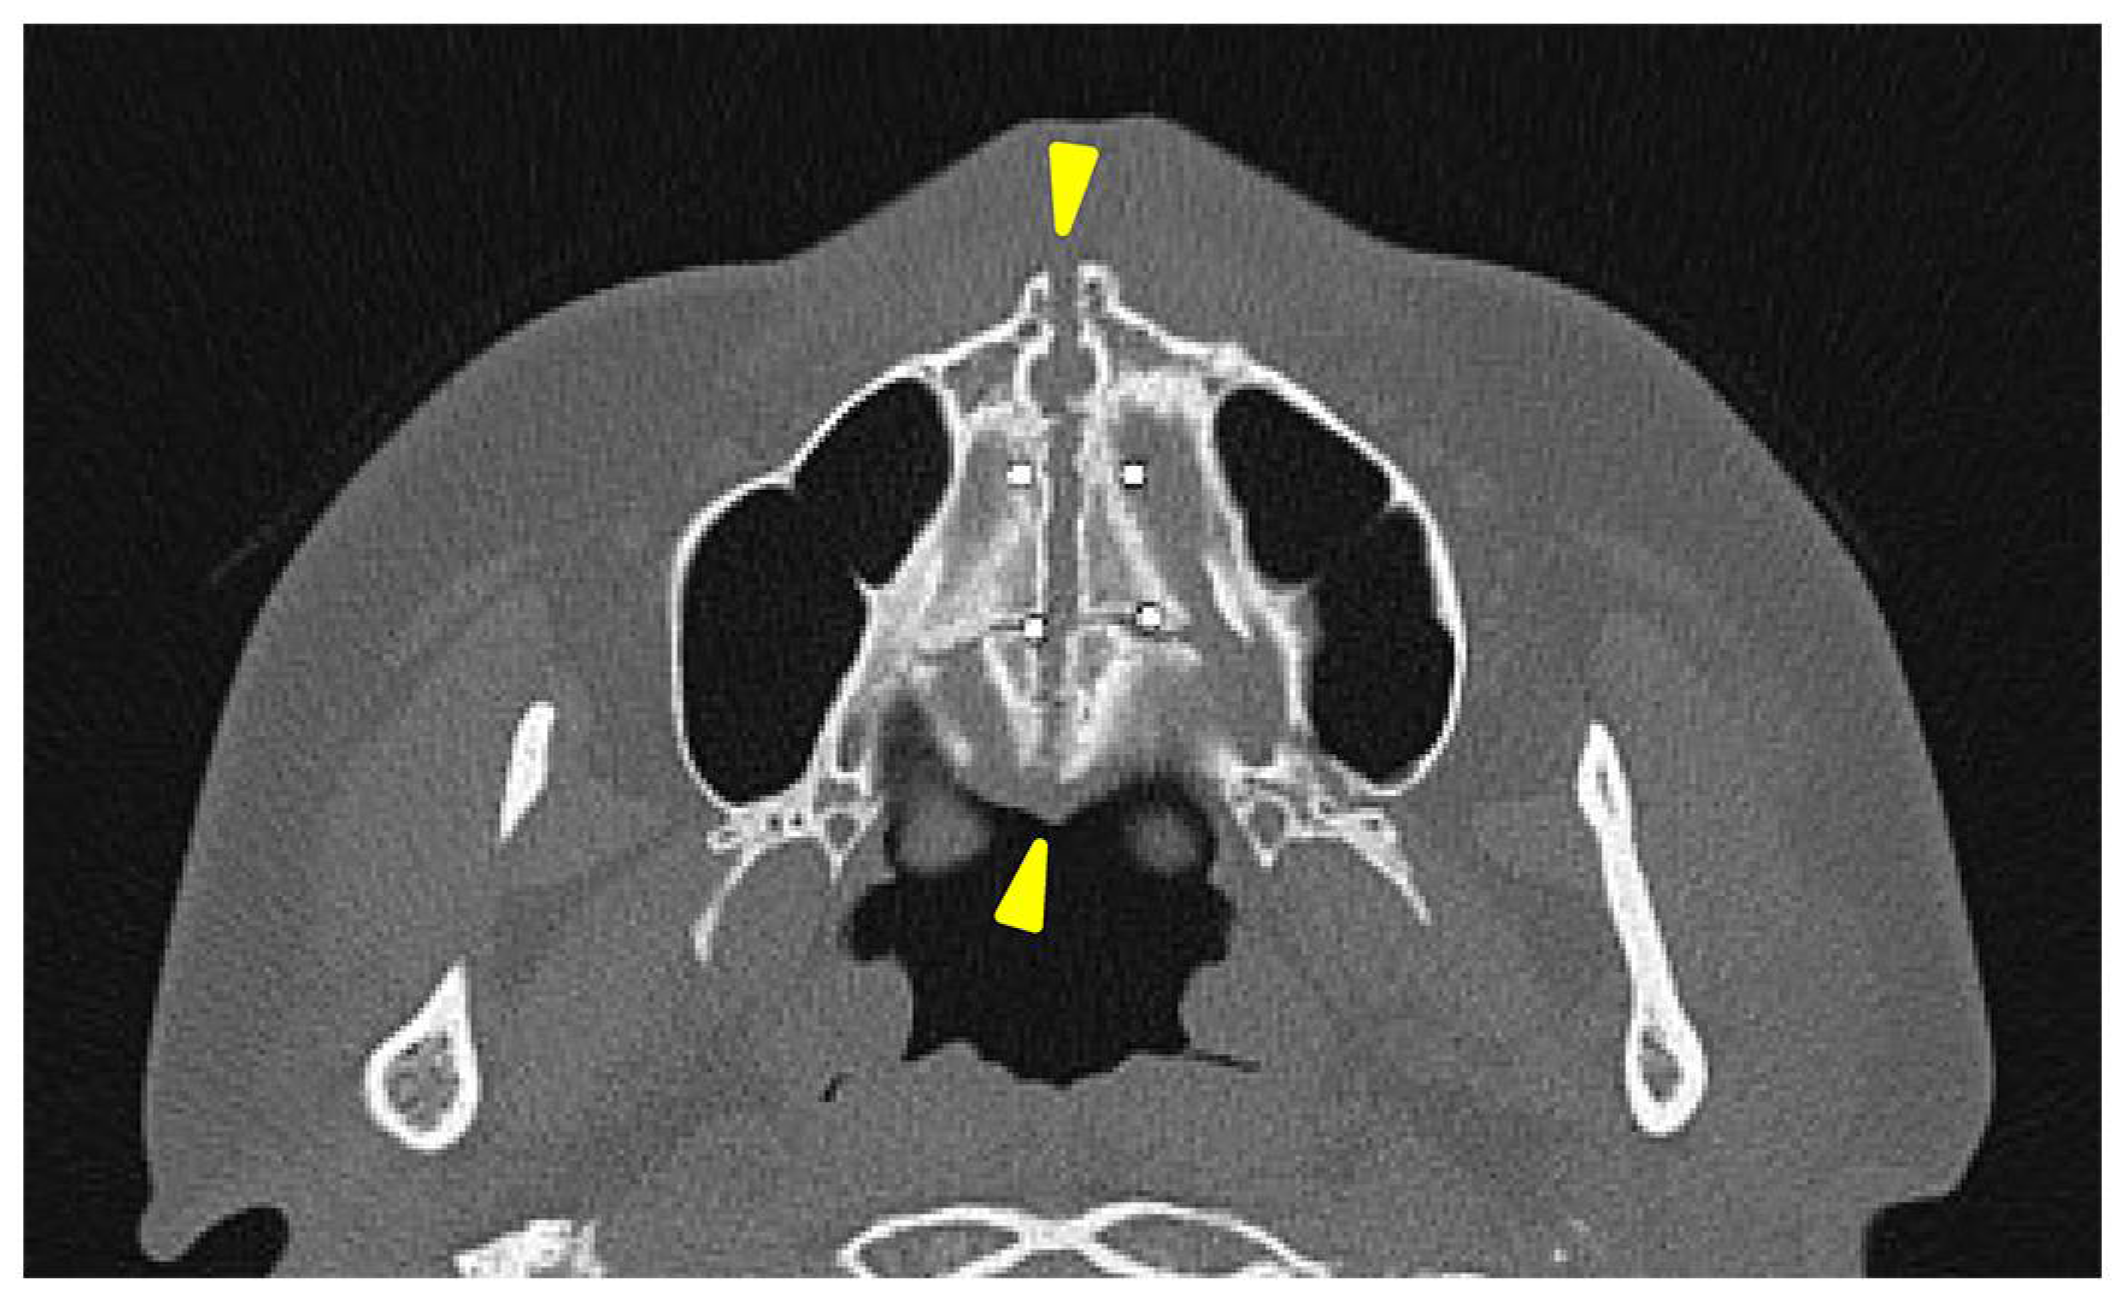

A separation of approximately 4 mm was observed in the midpalatal suture.

A head CT was performed on the same day. The axial slices revealed a 4 mm wide separation of the midpalatal suture (

Figure 3). A fracture of the left maxilla was also observed. The line of this fracture extended from the orbital floor and the anterior surface of the maxilla (